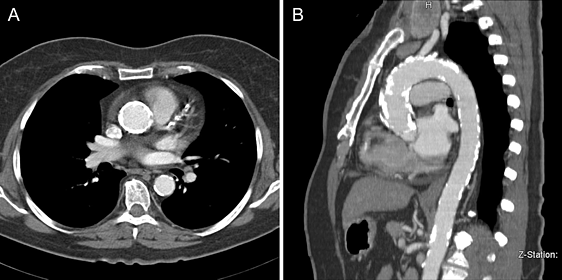

- МСКТ восходящей аорты с контрастированием – показано при постстенотическом расширении корня аорты;

- ЭхоКГ. ЭХОКГ позволяет определить: структуру клапана (двустворчатый клапан, утолщение створок, фиброз, кальциноз, вегетации), характер его движения (подвижность створок, степень открытия) и площадь отверстия; изменения корня аорты (постстенотическая дилатация), объем левого желудочка, выраженность гипертрофии левого желудочка, нарушения локальной сократимости левого желудочка (указывающие на ИБС), ФВ, объем левого предсердия, состояние других клапанов. Доплеровское исследование позволяет с высокой точностью определить градиент давления между аортой и левым желудочком.